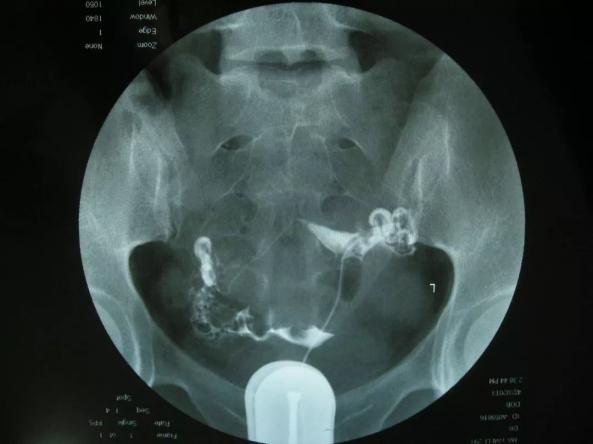

尿液是血液流經腎臟后過濾出來的液體,往往是一些代謝廢物,可檢查尿液酸堿度(pH值)、尿比重、尿膽原、尿膽紅素、尿酮體、尿隱血、尿白細胞、尿紅細胞、尿蛋白、尿糖、尿液顏色等指標,若有異常往往提示腎臟代謝和過濾存在損傷,需結合具體情況采取相應的治療措施。

泌尿外科專家提示:尿常規是臨床檢驗中三大常規項目之一,可以了解人體代謝狀態,尤其是泌尿系統的健康狀態,尿常規檢查包括以下幾個方面,一、理化特性,如酸堿度、比重、顏色等;二、特殊化學成分,如酮體、膽紅素等;三、細胞成分,如白細胞、紅細胞、上皮細胞等,若尿液中出現白細胞,提示可能存在尿路感染;出現紅細胞,提示可能存在尿路出血。